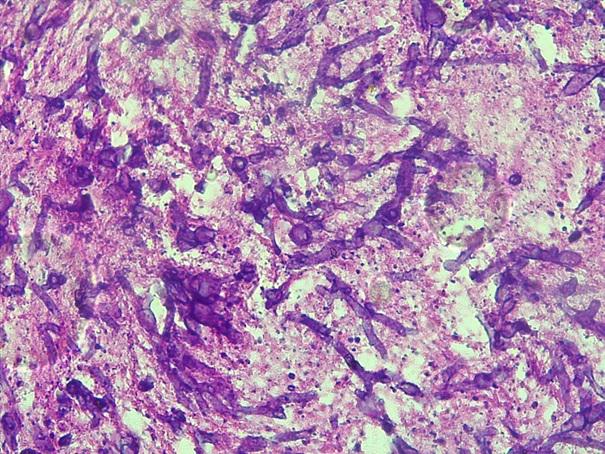

*Case 1 : Dr Ibrahim Adekanbi/ Dr Harrison

email: mamak97@yahoo.com

Clinical detail: Male, 45years, Tongue and Oral nodules and sores

Please, consult the virtual slides of Case 1 below.